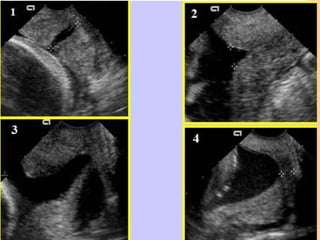

INCOMPETENCIA ITSMICO CERVICAL

SEMINARIO DE INCOMPETENCIA ITSMICO CERVICAL